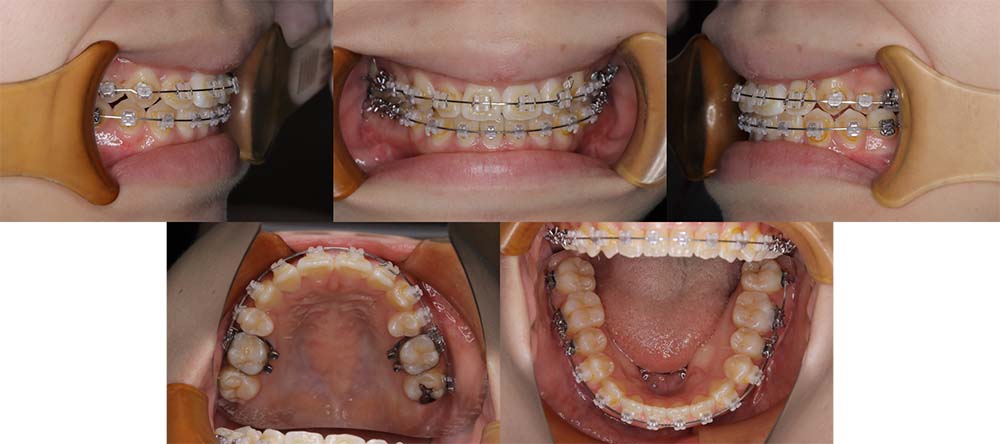

| 症例分類 | 顎変形症、叢生、側方偏移 |

| 診断名 | 下顎右側偏移を伴う上下叢生 |

| 主訴 | 歯並びがガタガタ、顎が右にずれている |

|---|---|

| 年齢 | 25歳4ヶ月 |

| 性別 | 女性 |

| 抜歯部位 | 上の左右第一小臼歯 |

| 使用装置 | 表側のワイヤー装置+外科矯正(手術を併用した治療) |

| 治療期間 | 2年1ヶ月 |

| 保定装置 | 固定式保定装置、取り外し式保定装置(8時間) |

| 費用 |

保険適応 [検査・診断等] 2万円程度 [装置装着] 5〜7万円程度 [調整料] 2,000〜7,000円程度/回 [手術前検査等] 2万円程度 [保定装置等] 4万円程度 合計18〜25万円程度 |

下顎の右側に偏移があり、骨格的にも受け口だったため、上顎両側第一小臼歯を抜去して、上下顎の手術を併用して治療を行いました。術前は前歯が反対のかみ合わせになり、初診時より咬合、顔貌は一旦悪くなります。術前矯正を1年7ヶ月した後に手術を行いました。

術後の顎間ゴムをしっかりと使用していただけたため、術後7ヶ月で治療が終了することができました。また、顎の歪みが残っていたため矯正治療終了後におとがい形成術をして、下顎の偏移を改善しました。

顎の歪みも下顎の前方感も改善することができ、上下のかみ合わせもしっかりと咬合することができました。